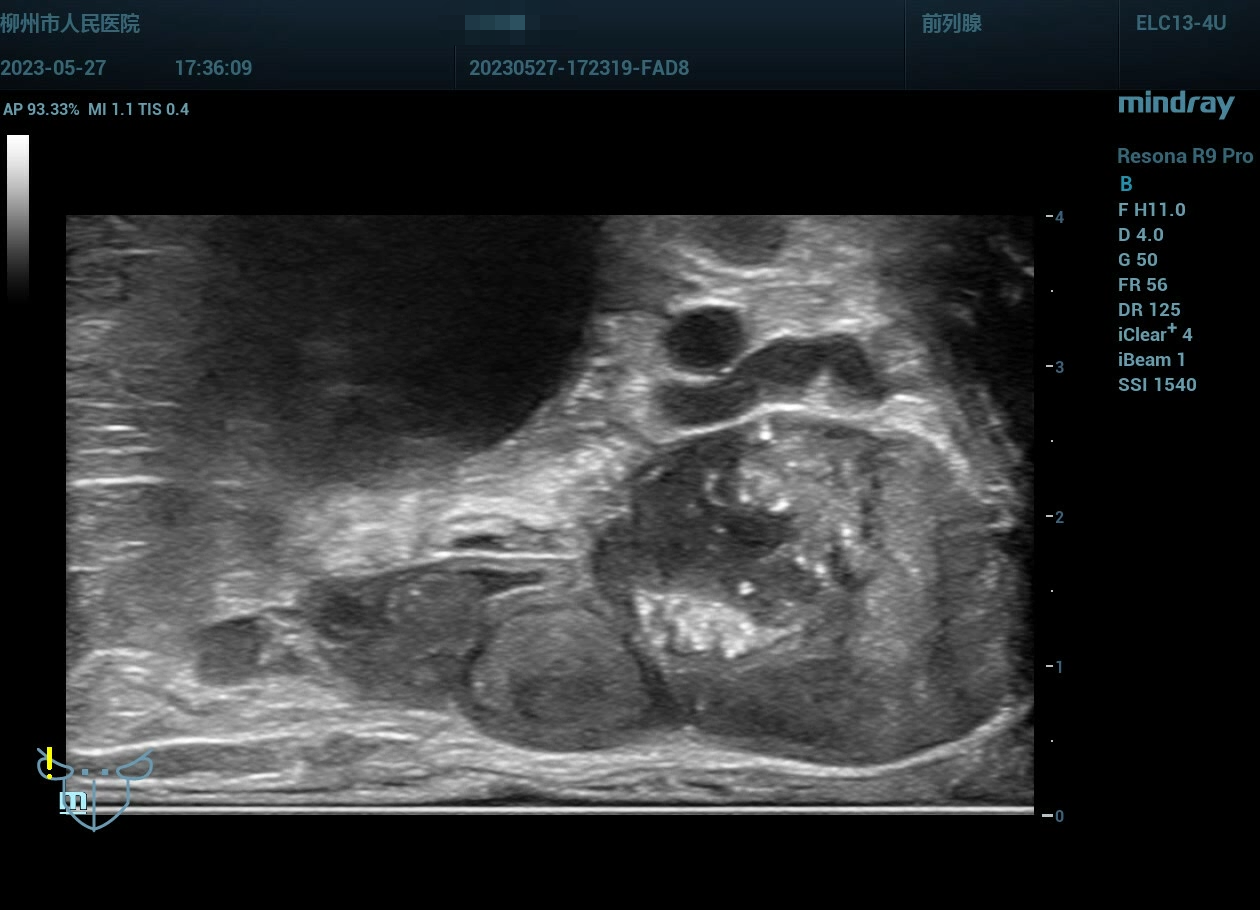

病史为年轻的男性,主要症状为尿痛、血精。

精囊腺的超声图像表现:肿胀、回声紊乱。